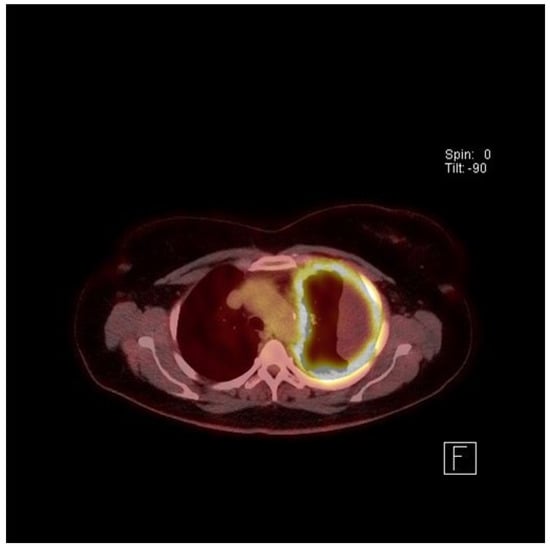

- Yildirim, H.; Metintas, M.; Entok, E.; Ak, G.; Ak, I.; Dundar, E.; Erginel, S. Clinical value of fluorodeoxyglucose-positron emission tomography/computed tomography in differentiation of malignant mesothelioma from asbestos-related benign pleural disease: An observational pilot study. J. Thorac. Oncol. 2009, 4, 1480–1484. [Google Scholar] [CrossRef]

- Kruse, M.; Sherry, S.J.; Paidpally, V.; Mercier, G.; Subramaniam, R.M. FDG PET/CT in the management of primary pleural tumors and pleural metastases. AJR Am. J. Roentgenol. 2013, 201, W215–W226. [Google Scholar] [CrossRef]